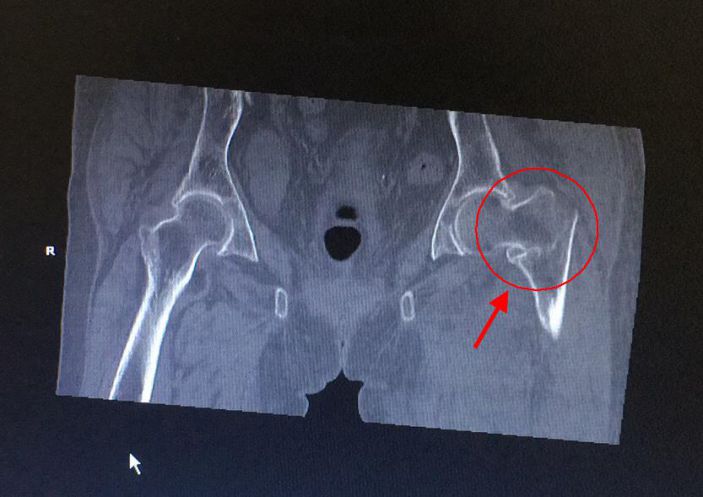

發布時間:2018-03-28 閱讀:3067 3月11日,康美醫院成功爲一名左股骨粗隆間粉碎性骨折的百歲老人開展股骨近端髓内釘(PFNA)内固定手術。

黃婆婆,女,100歲,上塘人,因走路時不慎跌倒,左臀部着地,緻使左髋部疼痛、活動受限,後至某三甲醫院住院治療4天。因高齡,合并有高血壓、老年性退行性心瓣膜病、動脈硬化性腎病、老年性骨質疏松,該醫院不敢爲其手術治療。3月10日,患者轉診至康美醫院外四科(骨科)。

康美醫院外四科随即請内科、麻醉科等相關科室主任會診,經綜合評估,拟定詳細的治療方案。外四科吳主任決定盡早爲其開展微創手術治療,3月11日,在麻醉科和内科的配合下,吳主任帶領團隊成功爲黃婆婆施行左股骨粗隆間骨折閉合複位股骨近端髓内釘(PFNA)内固定手術,整個手術過程隻用了25分鍾左右,手術非常成功。術後醫護人員對其進行周密觀察、精心護理,患者恢複良好,已經康複出院。